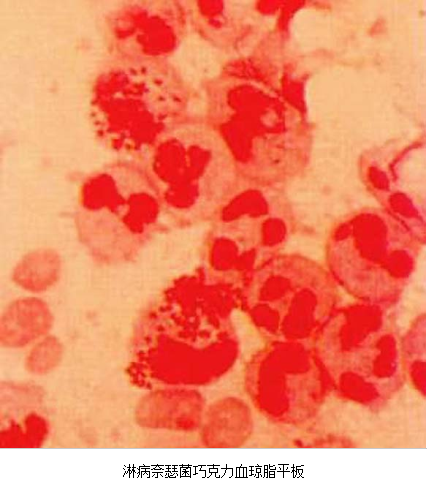

3.病原体检测 应作衣原体及淋病奈瑟菌的检测,以及有无细菌性阴道病及滴虫阴道炎。检测淋病奈瑟菌常用的方法有:①分泌物涂片革兰染色,查找中性粒细胞内有无革兰阴性双球菌,由于子宫颈分泌物的敏感性、特异性差,不推荐用于女性淋病的诊断方法。②淋病奈瑟菌培养,为诊断淋病的金标准方法。③核酸检测,包括核酸杂交及核酸扩增,尤其核酸扩增方法诊断淋病奈瑟菌感染的敏感性及特异性高。检测沙眼衣原体常用的方法有:①衣原体培养,因其方法复杂,临床少用。②酶联免疫吸附试验检测沙眼衣原体抗原,为临床常用的方法。③核酸检测,包括核酸杂交及核酸扩增,尤以后者为检测衣原体感染敏感、特异的方法。但应做好质量控制,避免污染。